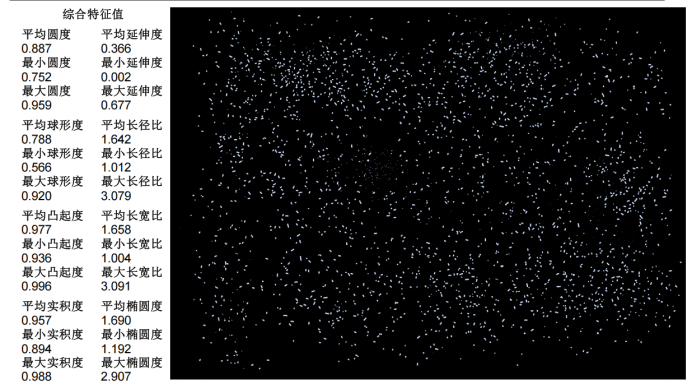

2.形貌特征:平衡 “成型性” 與 “溶出性”

擠出微丸的形貌需兼顧成型穩定性與藥物溶出效率,ZMS850 的檢測結果提供了精準判斷:

圓度與球形度:平均圓度 0.887,平均球形度 0.788,雖低于蔗糖丸芯,但符合擠出工藝微丸 “圓度≥0.80、球形度≥0.75” 的要求,可減少服用時的胃腸道刺激;

延伸度與橢圓度:平均延伸度 0.366,平均橢圓度 1.690,說明微丸雖非完美球體,但形狀規則,無明顯變形或破損,確保每粒微丸的藥物含量均勻;

凸起度與實積度:平均凸起度 0.977,平均實積度 0.957,反映微丸表面無明顯凹陷或孔隙,避免藥物在儲存過程中吸潮變質。